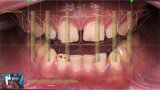

Způsobuje kojení zubní kaz?